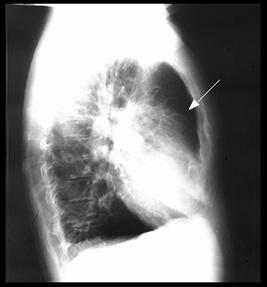

Rx cord-pulmon: circulatie pulmonara 'incarcata' cu ramurile AP dilatate in hiluri si extremitati 'retezate' avind periferie mult mai clara decat normal, bombare a conului arterei pulmonare, semne de hipertrofie VD

Imagine radiologica de HTP primara

Imagine Rx. de profil cu HVD Aspect CT de HTP primara